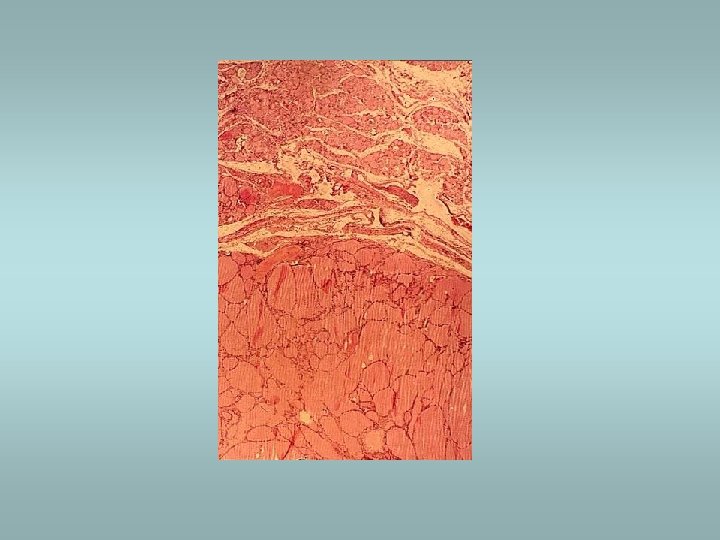

Riedel’s fibrosing thyroiditis ü Thyroid replaced by fibrous tissue ü Fibrous tissue extends and penetrate into the surrounding neck structures ü May be mistaken for infiltrating neoplasm